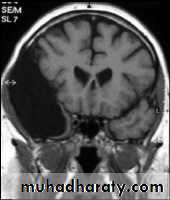

CORONAL SECTION OF BRAIN ( T1w post contrast injection)

Coronal T1-weighted MRI image through a brain lesion showing homogeneity of the lesion, lack of a perceptible wall, lack of internal complexity, and CSF signal intensity. There is associated remodeling of the adjacent calvarium and brain displacement. These imaging features are typical of an arachnoid cyst.